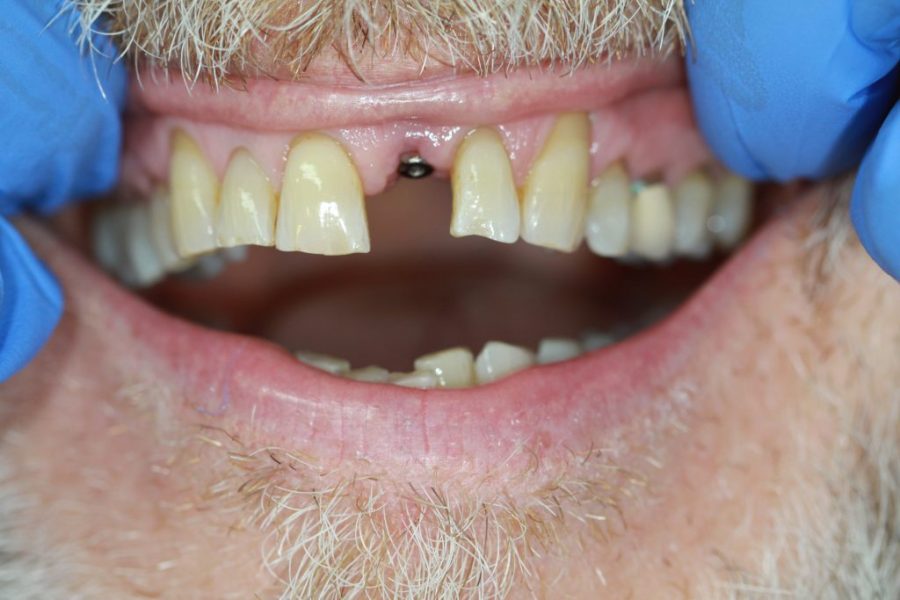

Henry’s Story: A Full Smile Makeover

Henry’s broken teeth were impacting his confidence. With a combination of root canal therapy, laser gum surgery, crowns, and dentures, we restored his smile over four weeks. Now, his family and grandchildren are thrilled with his transformation.